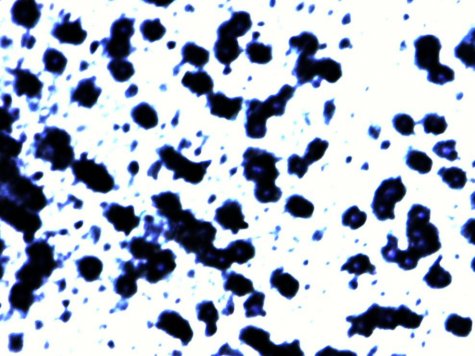

不同结构的改性果胶诱导细胞凋亡的情况见图1.

图1:不同小分子果胶对MDA-MB-231细胞生长曲线的影响

备注:control为空白组,A、B、E为相同分子量和酯化度但生产工艺不同,A和F是不同酯化度的改性果胶。

其中A为我公司酶解工艺生产的小分子果胶。诱导MDA-MB-231细胞凋亡效果最好。且酶法生产的小分子果胶同时对正常细胞的损伤最小。